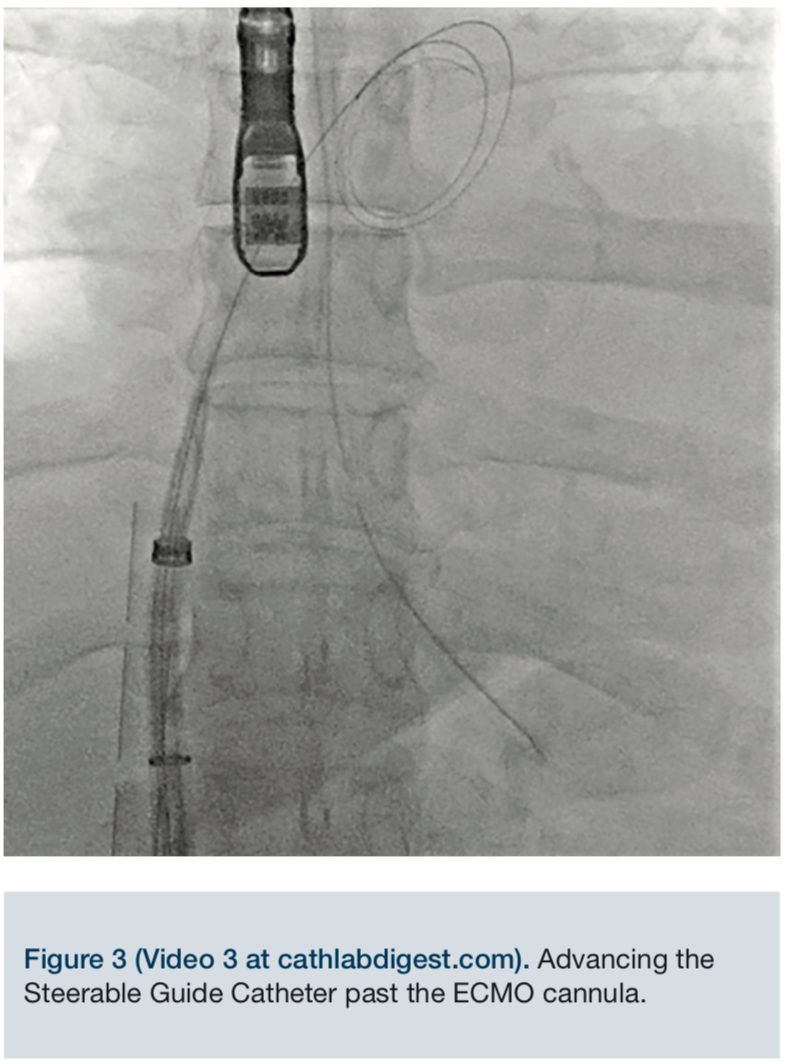

Video 3. Advancing the Steerable Guide Catheter past the ECMO cannula.

Through a 6 French femoral venous sheath, an 0.032-inch Amplatz Extra Stiff guidewire (Cook Medical) was placed into the superior vena cava and the sheath removed. An 8 French SL1 sheath (St. Jude Medical) was advanced over the guidewire into the superior vena cava. Care was taken not to interfere with the ECMO cannula. Using standard technique under transesophageal guidance, the 71cm BRK transeptal needle (St. Jude Medical) was used to obtain a high and posterior puncture. The SL sheath was advanced into the left atrium. A ProTrack pigtail wire (Baylis Medical) was advanced into the left atrium. The 24 French steerable guide catheter was successfully negotiated across the intra-atrial septum and advanced into the left atrium using appropriate maneuvers.